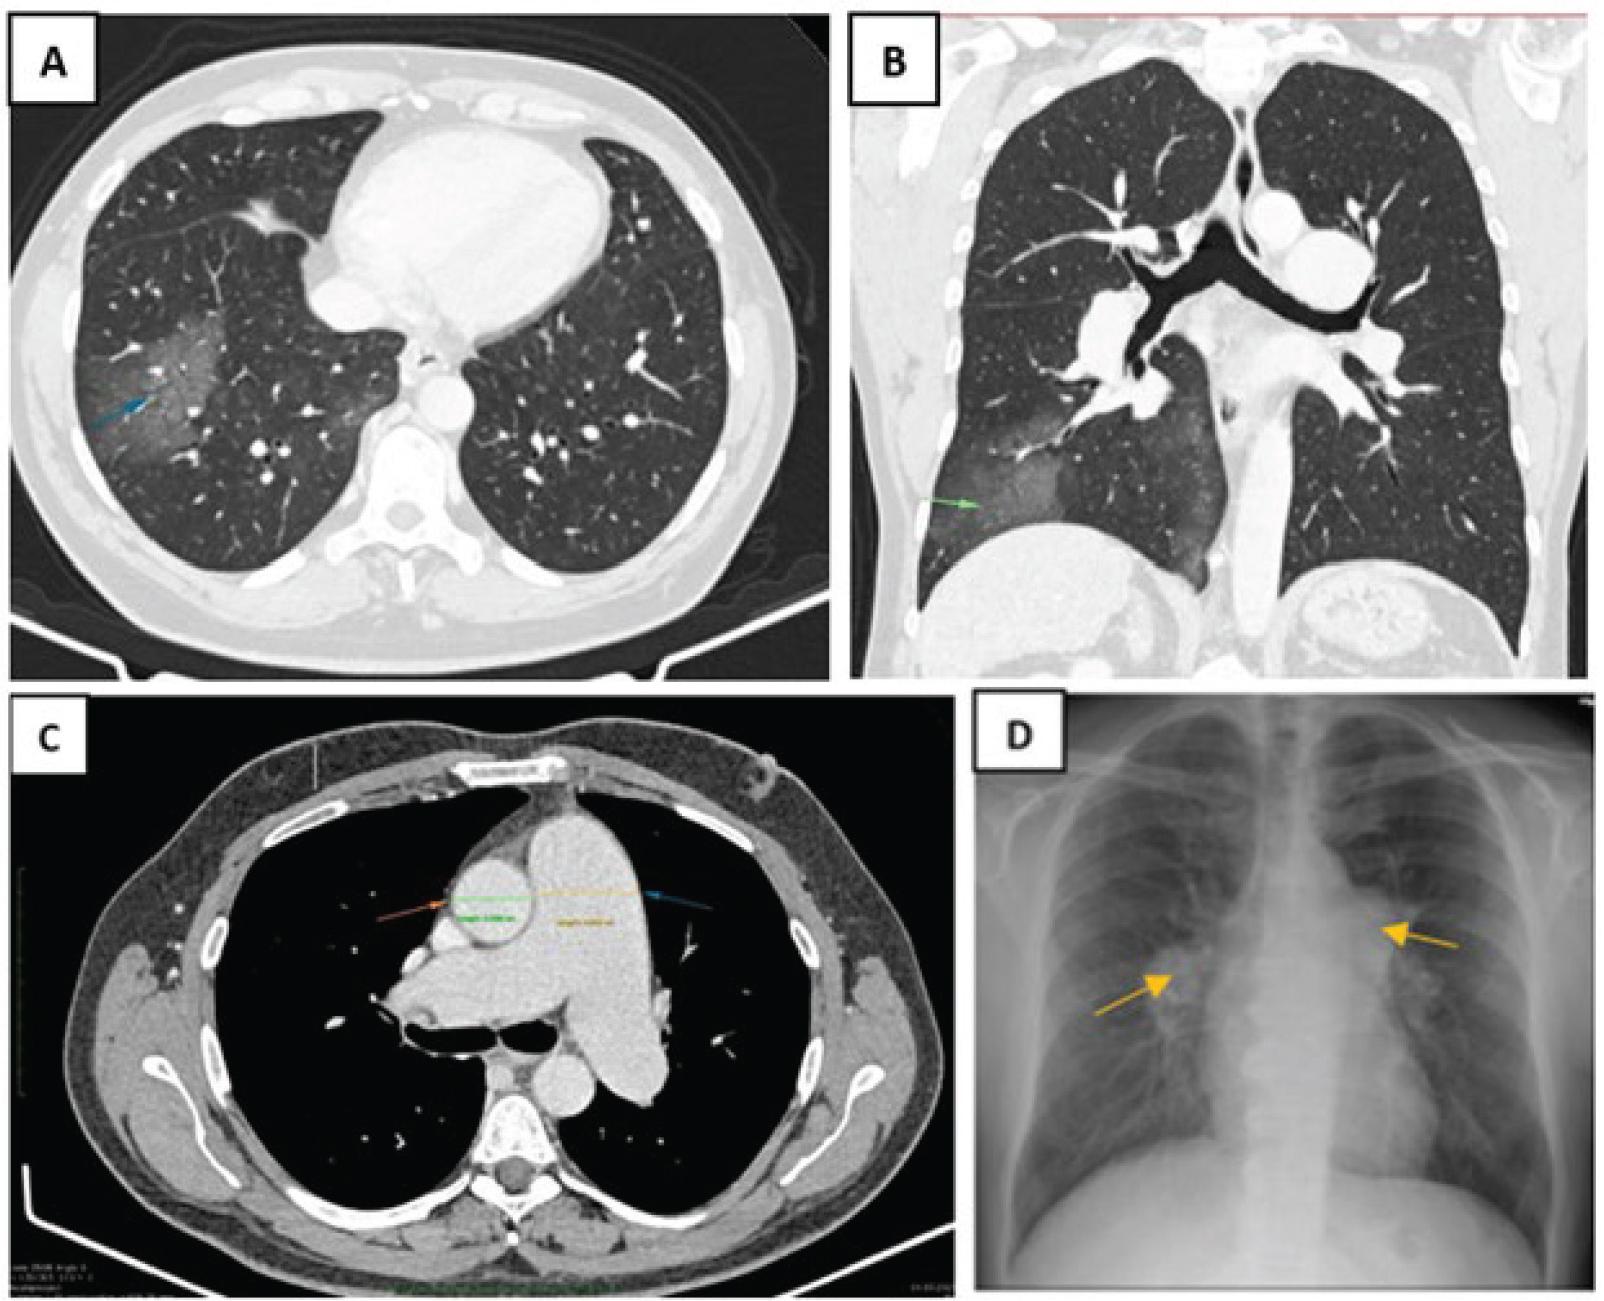

The chest X-ray showed bilateral hilar opacities with a polycyclic appearance (Figure 1D), which, in the context of the patient’s smoking history and haemoptysis, raised the initial suspicion of a bronchopulmonary neoplasm. This prompted further evaluation through high-resolution contrast-enhanced computed tomography (HRCT) and bronchoscopy.

(A) Axial CT scan, lung window; (B) Coronal CT scan, lung window – ground-glass opacities (blue arrow A, green arrow B) with a confluent lobular pattern are visible in the right basal pyramid, involving both peribronchovascular and peripheral regions, secondary to recent episodes of haemoptysis. (C) Pulmonary arterial phase of thoracic CT revealed significant enlargement of the main pulmonary artery (blue arrow), which exceeded the diameter of the adjacent ascending aorta (red arrow) – a classic radiologic feature suggestive of PH. (D) Chest X-ray at first check-up showed hilar opacities with a polycyclic appearance. PH, pulmonary hypertension.

CT imaging showed multiple pathological changes consistent with chronic liver disease and pulmonary vascular involvement. Ground-glass opacities with a confluent lobular pattern were identified within the right basal pyramid, involving both peribronchovascular and peripheral pulmonary regions (Figures 1A and 1B). The ground-glass opacities identified were interpreted as secondary to recent episodes of haemoptysis. No bronchiectasis or structural pulmonary abnormalities were observed. The pulmonary arterial system was significantly dilated (Figure 1C), with a main pulmonary artery diameter of 50 mm and symmetrical enlargement of both right and left pulmonary artery branches (37 mm each), indicating pulmonary arterial hypertension (PAH) (9, 10). In the upper abdomen, the liver appeared enlarged, involving the left and caudate lobes in particular, with a lobulated contour and heterogeneous parenchymal density. Focal areas of steatosis were noted, consistent with chronic liver disease. Multiple features indicative of PHT were identified, including dilatation of the portal vein (17.5 mm), inferior mesenteric vein (16.5 mm) and inferior vena cava (28 mm), along with paraumbilical vein enlargement, perigastric collateral circulation and the presence of oesophageal and perioesophageal varices. The spleen was surgically absent (status postsplenectomy), but three accessory spleens of variable sizes were identified, all exhibiting normal morphology. These imaging findings are indicative of advanced PHT secondary to hepatic cirrhosis, complicated by PAH and residual postsplenectomy anatomical variations.